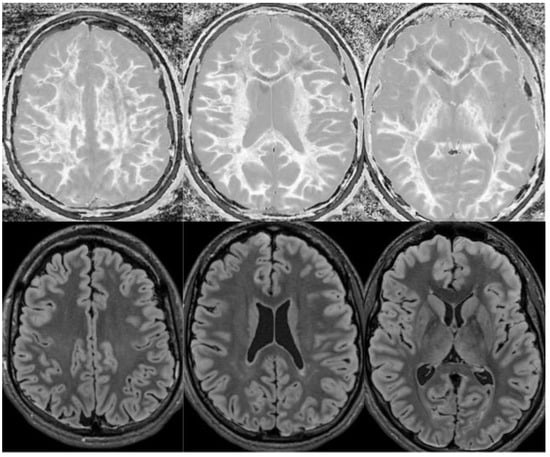

Figure 13.

Divided Subtracted Inversion Recovery (dSIR) in a patient with multiple sclerosis (MS). Three axial narrow middle domain images in a patient with an acute MS flare at the level of the centrum semiovale (left), corona radiata (middle), and basal ganglia (right). TIshort = 350 ms. TIlong = 500 ms. TE = 7 ms, TR = 5000 ms. The white matter is not black as in Figure 9b. There is a widespread increased signal, though not a “white out” sign as described in Figure 14. This is an “intermediate” appearance but not considered normal.

We believe that dSIR is well suited to identifying generalized changes in white matter T1. We have described the “white out sign” as dSIR findings of a widespread and relatively homogeneous high signal throughout the white matter (Figure 14). This contrasts with normal, predominantly low-signal white matter. A third category of a widespread, less increased signal represents an intermediate form of the white out sign.

Figure 14.

Normal and abnormal divided Subtracted Inversion Recovery (dSIR) images. Narrow middle domain images in three patients at the level of the centrum semiovale. TIshort = 350 ms. TIlong = 500 ms. TE = 7 ms, TR = 5000 ms. The left image shows an example of the “white out sign”, with a diffusely increased signal throughout the white matter. The center image is an example of normal. The white matter has a mildly increased signal that is normal because TIshort = 350 ms nulls tissue with T1 values less than that of white matter. The image on the right has an intermediate appearance, probably abnormal but not a “white out”.